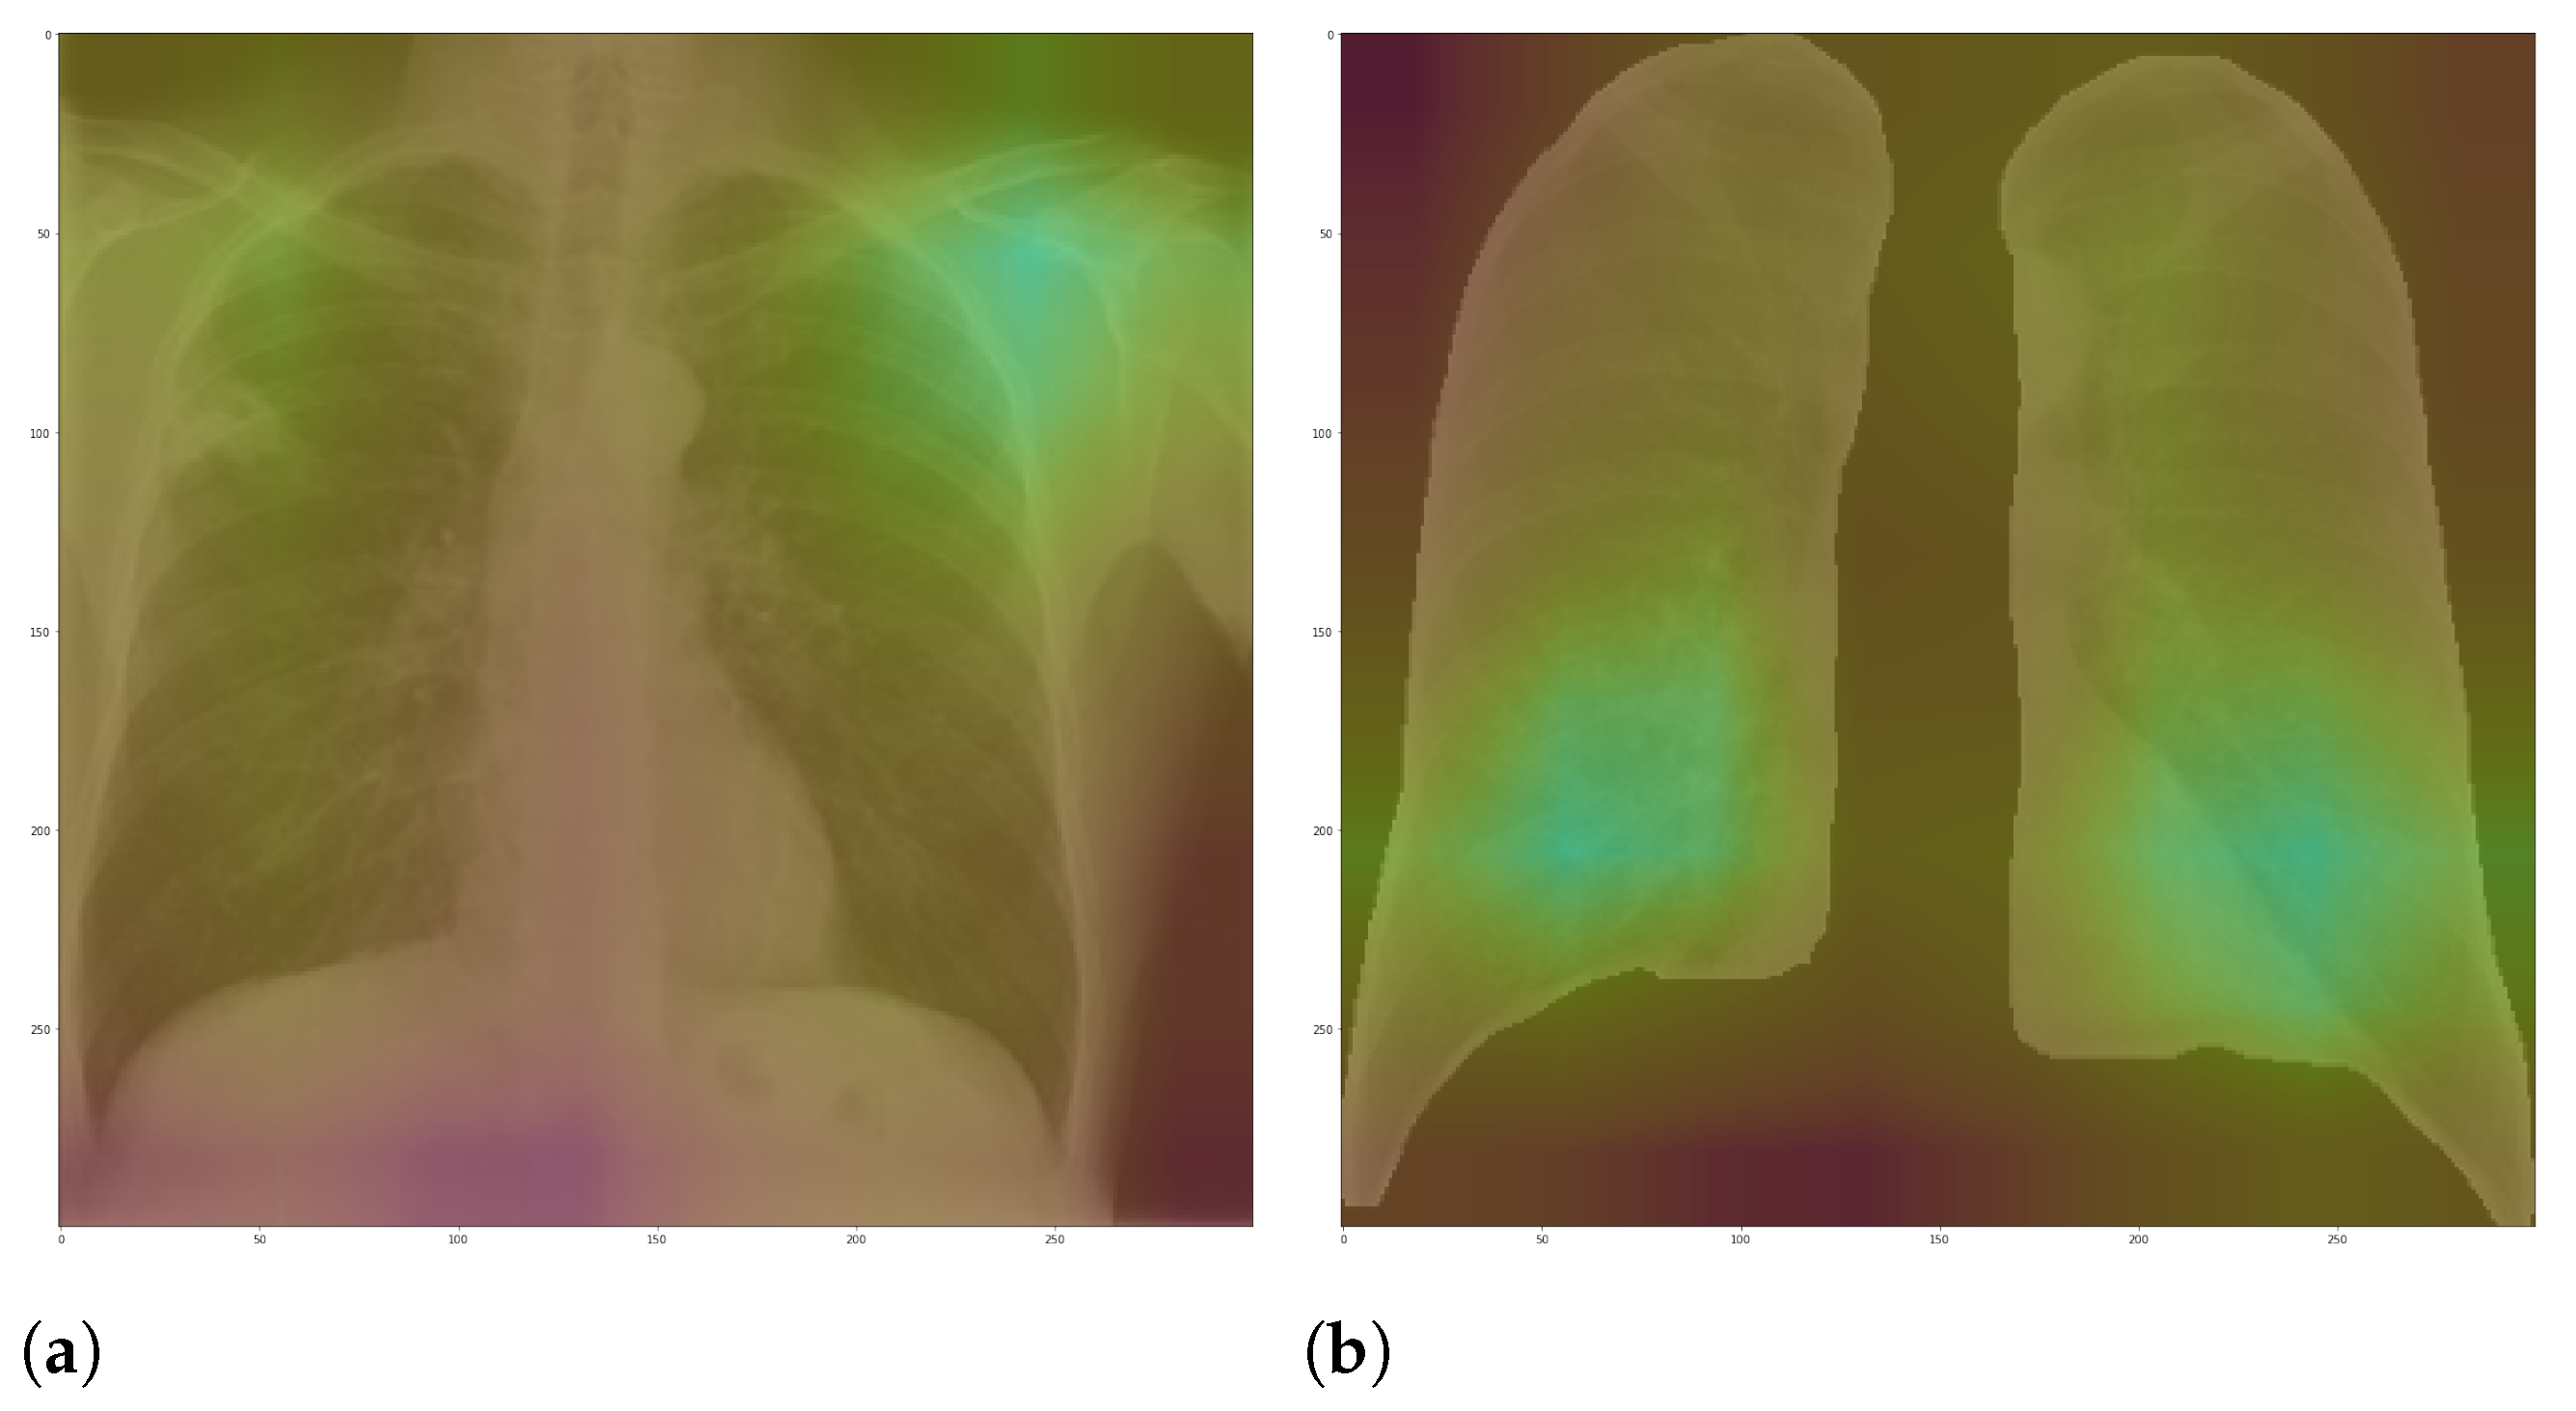

Figure 7 and

Figure 8 shows examples of important regions highlighted by LIME and Grad-CAM, respectively. In

Section 4, we will show that models trained using segmented lungs focus primarily on the lung area, while models trained using full CXR images frequently focus elsewhere.

For each image in the test set, we used LIME and Grad-CAM to find the most important regions used for the predicted class, i.e., regions that support the given prediction. We then summarized all those regions in a heatmap to show the most common regions that the model uses for prediction. Thus, we have one heatmap per classifier per class per XAI approach.

5.2. XAI

In this paper, we applied two XAI techniques: LIME and Grad-CAM. The reason for applying both is to evaluate the classification models thoroughly since they work differently. They have some significant differences and highlights: (i) LIME is model-agnostic, and Grad-CAM is model-specific; (ii) in LIME, the granularity of important regions is correlated to the granularity of the superpixel identification algorithm; (iii) Grad-CAM produces a very smoothed output because the dimension of the last convolution layer is much smaller than the dimension of the original input. Keep in mind that such techniques are not definitive. They can complement and corroborate with each other. Thus, we can increase the model reliability in a real-world context by using a more comprehensive approach.

Our XAI approach is novel in the sense that we explored a more general explanation instead of focusing on single examples. In the literature, there are many papers exploring LIME and Grad-CAM for a couple of handpicked examples. The main problem with such approaches is that the examples might have been eventually chosen to reach a specific result. In this paper, we applied the XAI techniques to each image in the test set individually and created a heatmap aggregating all individual results to represent a broader context, which indicates which portions of the CXR image the models have focused on for prediction.

Figure 10 and

Figure 11 demonstrate that the models using full CXR images are misleading because they focus a lot on the left and right uppermost regions, which is usually the location of burned-in annotations.